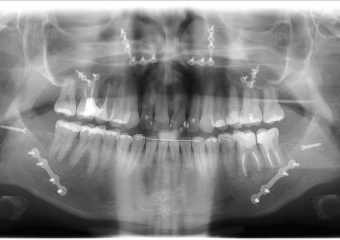

Rx Panorâmico Inicial

Rx panorâmico após a cirurgia